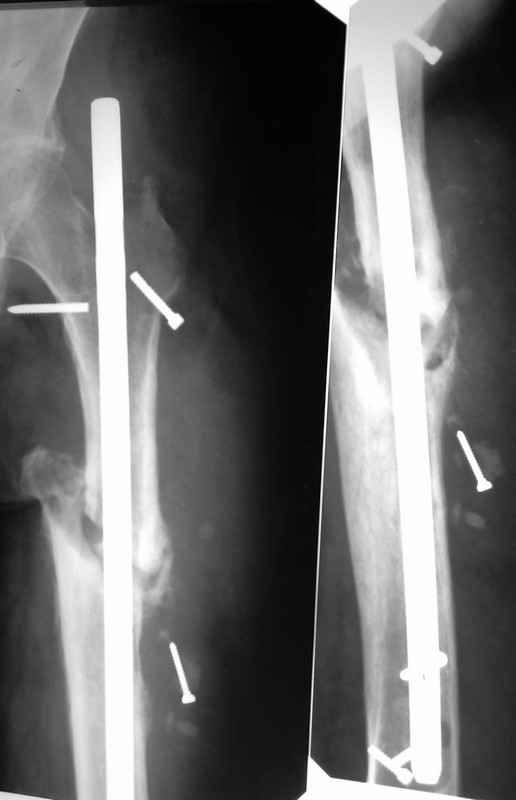

Здравствуйте уважаемые коллеги, прошу Вашего мнения относительно тактики лечения пациента М. 37 лет, рост 170 см. вес 140 кг. Анамнез: пострадал в рез. ДТП в 2004 году, лечился в одной из районных больниц гдебыл прооперирован DCP. в 2006 году перелом м/фиксатора с последующим реостеосинтезом стержнем Кюнчера без блокирования. в 2007 году перелом фиксатора после чего обратился в нашу клинику, где было произведено удаление гвоздя, БИОС L-360 mm D-12 mm с кортико-спонгиозной пластикой, в теч. 6-и мес. больной был под наблюдением динамизация ч-з 2 мес. после чего пациент исчез с поля зрения. Появился с жалобами на болезненность в месте перелома, укорочение ноги, в течении года поочередно в ягодичной области и н/3 бедра функционирующие свищи. На данный момент имеем свищ в н\3 бедра, укорочение ноги на 3 см, внешняя ротация.Произведена фистулография, взят посев из свищевого хода. Планируется: - Удаление м\фиксатора и всех винтов(за исключением проксимального) - I&D с рассверливанием до 16 мм. - кортикотомия, открытое устранение деформаций - БИОС стержнем L-360 mm D-12 mm с а.б. покрытием - бусы с ванкомицином в области свищей

Уважаемый Илья! Если я правильно понял, фистулография у Вас - вторая картинка, а ранки на первой фотографии в области нижних блокирующих винтов и приблизительно на уровне псевдоартроза. Хотелось бы уточнить, есть ли клинические проявления свища на уровне псевдоартроза, отделяемое и т. д. Это существенно влияет на план операции - если перелом неинфицирован,а инфекция только на уровне нижних блокирующих винтов, достаточно удалить конструкции, те, что доступны, не стоит гоняться за кончиками винтов, произвести остеосинтез по Илизарову (на уровне малого вертела стержни, конечно)с п о с т е п е нн о й коррекцией угловой и ротационной деформаций. Параллельно ревизовать место расположения нижнего блокирующего винта, рассверлить, почистить, дренировать.